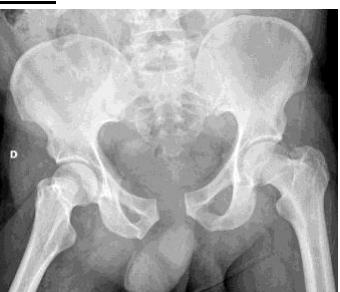

A 13 years old patient, she is known to have idiopathic scoliosis. X-ray pelvis was requested for her.

- 1. Mention the name of the sign seen the X-ray.

- Risser sign

- 2. How it can help in taking decision the management?

- By assessing potential of growth to evaluate potential deformity progression (e.g. scoliosis)